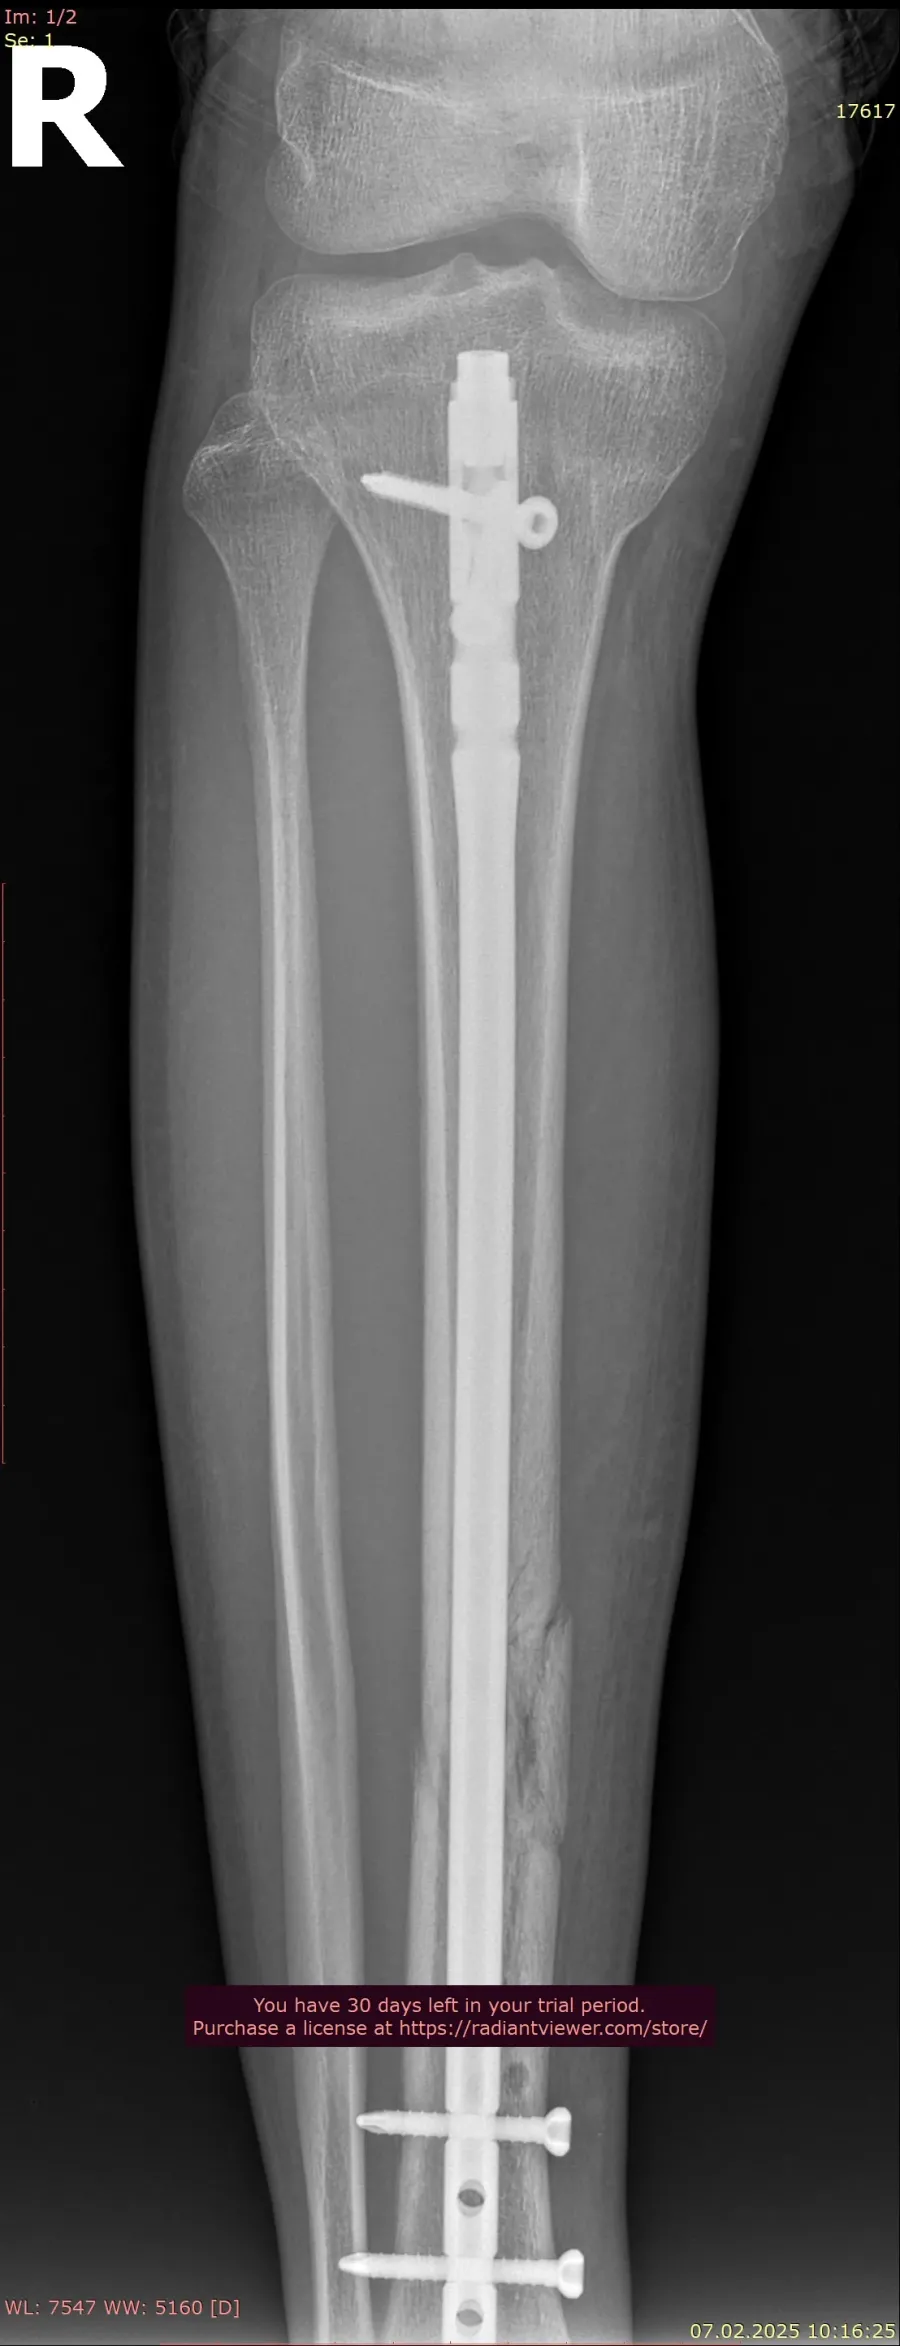

Дана методика дає можливість малоінвазивного остеосинтезу (через невеликі розрізи вводити фіксуючі стержні в канал кістки, які стабільно утримують перелом кістки), інформують "Вікна" з посиланням на Обласну дитячу лікарню.

Які ж переваги даного методу? Це надійна стабілізація перелому, дуже рання реабілітація пацієнта, зменшення післяопераційного періоду та ускладнень, скорочення термінів перебування в стаціонарі. Дитина не потребує додаткової фіксації гіпсовими пов’язками та має можливість раннього навантаження та швидкого відновлення функціонування кінцівки.